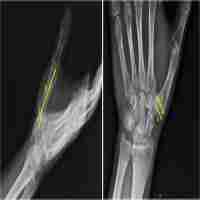

| Abstract | Background The purpose of this study was to introduce arthroscopic partial trapeziectomy and tendon interposition for the treatment of symptomatic thumb carpometacarpal arthritis of Eaton stage II or III. Methods From August 2001 to April 2009, 23 patients with thumb carpometacarpal arthritis were treated using this technique. Pain score, range of motion, and pinch strength were clinically evaluated and compared with the preoperative values after a minimum follow-up duration of 24 months. Results Significant reduction in pain score and increases in range of motion and pinch strength were found (all p < 0.001) after a 2-year follow-up. The mean ± SD (median) postoperative pain score was 1.0 ± 0.7 (1.0) at rest and 1.3 ± 0.9 (1.0) during daily activities. The postoperative range of motion was 19.1° ± 4.2° (20°) for extension and 35.7° ± 7.1° (35.0°) for flexion, and the postoperative pinch strength was 86.5 % ± 19.9 % (90.0 %). No complications were observed in our patient series. Conclusions Arthroscopic partial trapeziectomy and soft tissue interposition could be an alternative treatment method for patients with symptomatic thumb carpometacarpal arthritis of Eaton stage II or III. |